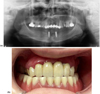

These sequelae impaired mastication, speech, and aesthetics and caused mandibular pain. A conservative approach was chosen in the maxilla, with a fixed bridge from 13 to 23 and crowns on 17 and 27 (Fig. 2A–B). All mandibular teeth were removed, and two implants were placed at 33 and 43 with Locator attachments to retain a complete removable prosthesis (Figs. 2A–2B). Regular follow-up and periodontal maintenance therapy have been introduced to avoid implant failure to ensure long-term survival of the rehabilitation and conservation of the remaining teeth.

Fig. 2 (A) Post-operative panoramic radiograph (June 2025) of case 1 after extractions and placement of two mandibular implants with Locator® attachment system. (B) Intraoral view in occlusion showing the maxillary bridge and mandibular overdenture on Locator® attachments. |